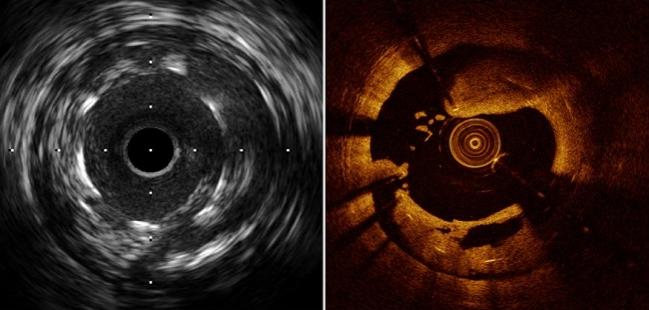

Imaging Guided PCI (IVUS / OCT)

Advanced Coronary Imaging Sessions